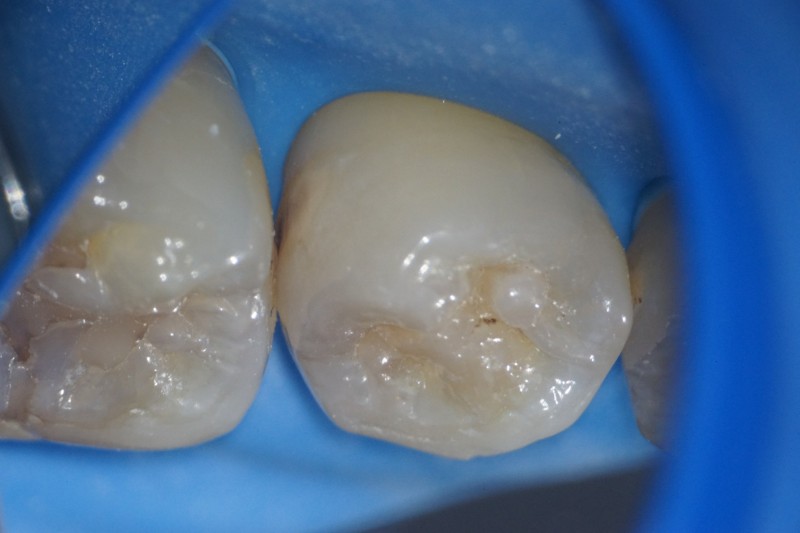

5番の隣接面が黒くなって虫歯になっています。

マイクロスコープで確認しながら、慎重に虫歯にアプローチしていきます。

虫歯を取り除きました。少し深いです。